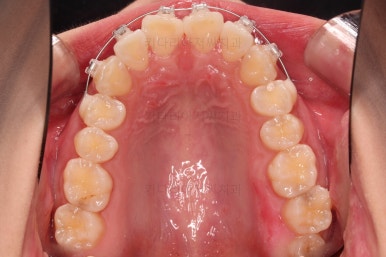

초진 시 입안의 모습입니다.

어금니 쪽은 약간 삐뚤긴 하지만 꼭 교정해야 할 정도는 아니고, 불편감 없이 비교적 잘 맞물리는 상태였습니다.

다만, 앞니ㅉㄱ이 공간이 부족해서 중간 치아들이 많이 회전되어있는데, 이를 환자분들의 표현에 따르면 "나비치아" 라고 부릅니다.

위아래 중간 앞니가 모두 나비치아처럼 되어있고요.

윗니가 아랫니보다 앞쪽으로 나와 있는 모습에 아래앞니가 윗니쪽으로 깊숙이 올라간 "과개교합" 양상을 보였습니다.